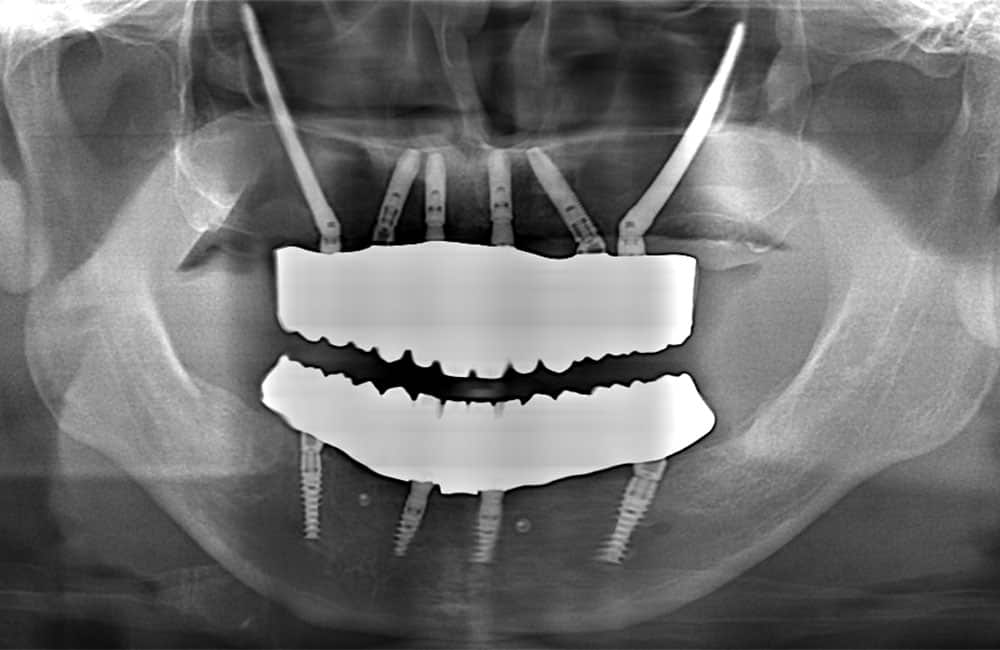

他院でザイゴマインプラント治療を受けた後、仮歯の噛み合わせが悪いため噛みづらく顔貌も変わってしまった。また頬に違和感を感じたため当院を受診。

術前のパノラマX線画像

左右のザイゴマインプラントが頬骨から大きく飛び出し頬を触ると違和感がある -

術後のパノラマX線画像

前方のインプラントは残し、他院埋入のザイゴマインプラントを除去し、同時に新しいザイゴマインプラントを適切な位置に再埋入を行っております。治療後数年経過しておりますが良好な状態を保っております。